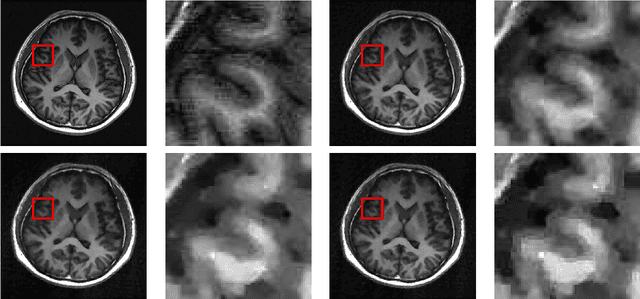

Abstract:Image super-resolution is a process to enhance image resolution. It is widely used in medical imaging, satellite imaging, target recognition, etc. In this paper, we conduct continuous modeling and assume that the unknown image intensity function is defined on a continuous domain and belongs to a space with a redundant basis. We propose a new iterative model for single image super-resolution based on an observation: an image is consisted of smooth components and non-smooth components, and we use two classes of approximated Heaviside functions (AHFs) to represent them respectively. Due to sparsity of the non-smooth components, a $L_{1}$ model is employed. In addition, we apply the proposed iterative model to image patches to reduce computation and storage. Comparisons with some existing competitive methods show the effectiveness of the proposed method.